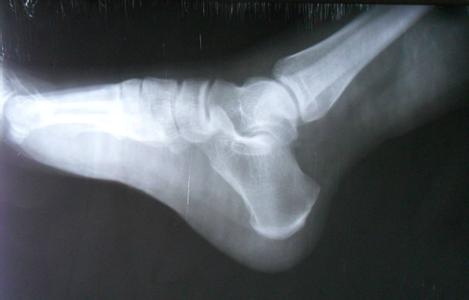

痛风

痛风性关节炎是由于尿酸盐沉积在关节囊、滑囊、软骨、骨质和其他 ...